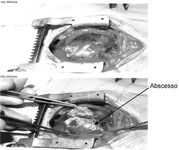

Cirurgia por via aberta em um bebê com pericardite purulenta; o abscesso é indicado pela seta

Karuppaswamy V, Shauq A, Alphonso N. BMJ Case Reports 2009; doi:10.1136/bcr.2007.136564